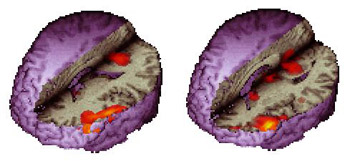

Orthogonal Views

Orthogonal views refer to a set of mutually perpendicular images. This localizes a given region of activation to the three axes that define the volumetric shape of the brain.

Case 2

Right handed adult male patient with intractable seizures coming from the left temporal pole, performing a language task consisting of listening to a story. No structural lesion was found in this region. A left temporal resection is planned. The orthogonal views permit evaluating of the extent of the language areas and the distance between its anterior border and the temporal pole (orange line). The neurosurgeon may use these findings as a guide to tailor the temporal resection.